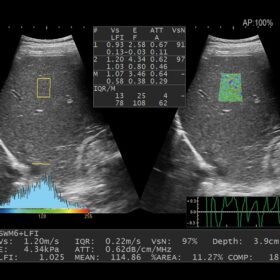

Ultrasound ARIETTA 750 VE – Image Gallery and Videos

Radiology 2D, Color, Contrast and Elasto mode

Radiology

Be prepared for various clinical cases.

- Highly sensitive B-mode and Color Mode

- Advanced Elastography features